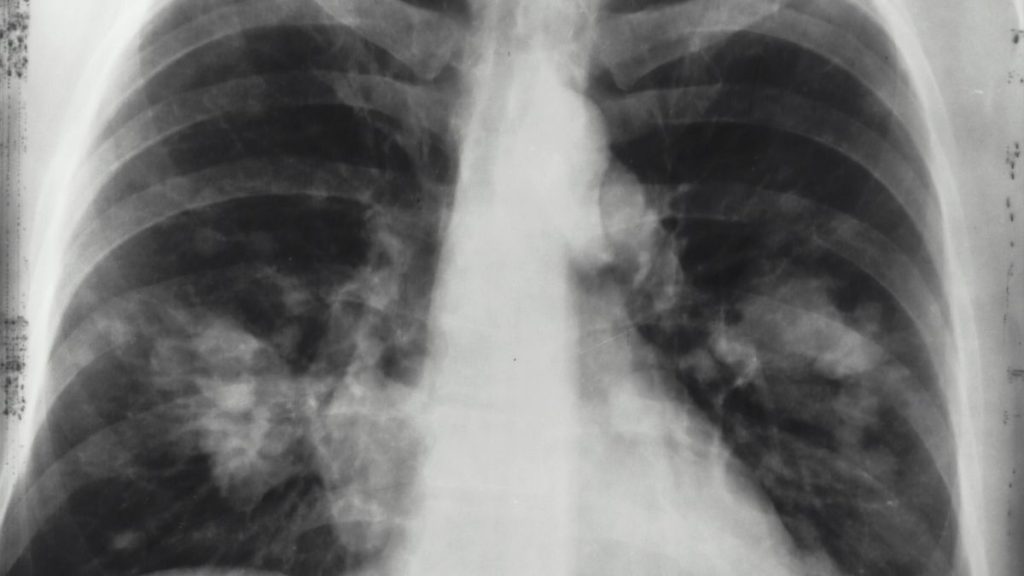

O diagnóstico é realizado com base em sintomas, sinais clínicos e achados na radiografia torácica. No entanto, a radiografia de tórax não é obrigatória, nomeadamente perante a suspeita de pneumonia sem critérios de gravidade.